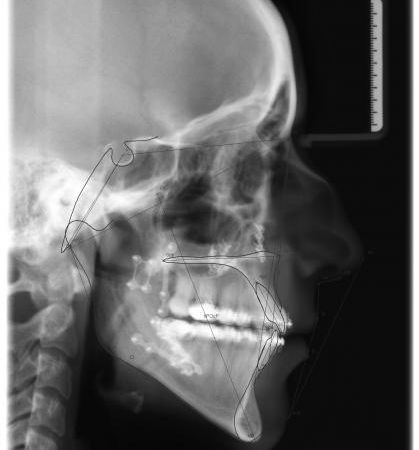

Röntgenbefund

Zu Behandlungsbeginn und nach der Operation

Die Verlagerung der Kieferbasen, v.a. im Unterkiefer, ist deutlich zu erkennen. Ferner sieht man auf dem rechten Bild die Metallplatten aus Titan, die die Knochenfragmente während der Heilungsphase in der gewünschten Position zusammenhalten. So wird frühzeitig sichergestellt, daß der Patient wieder normal kauen kann. Die Metallplatten können nach ca. 6 Monaten in einem Zweiteingriff entfernt werden.